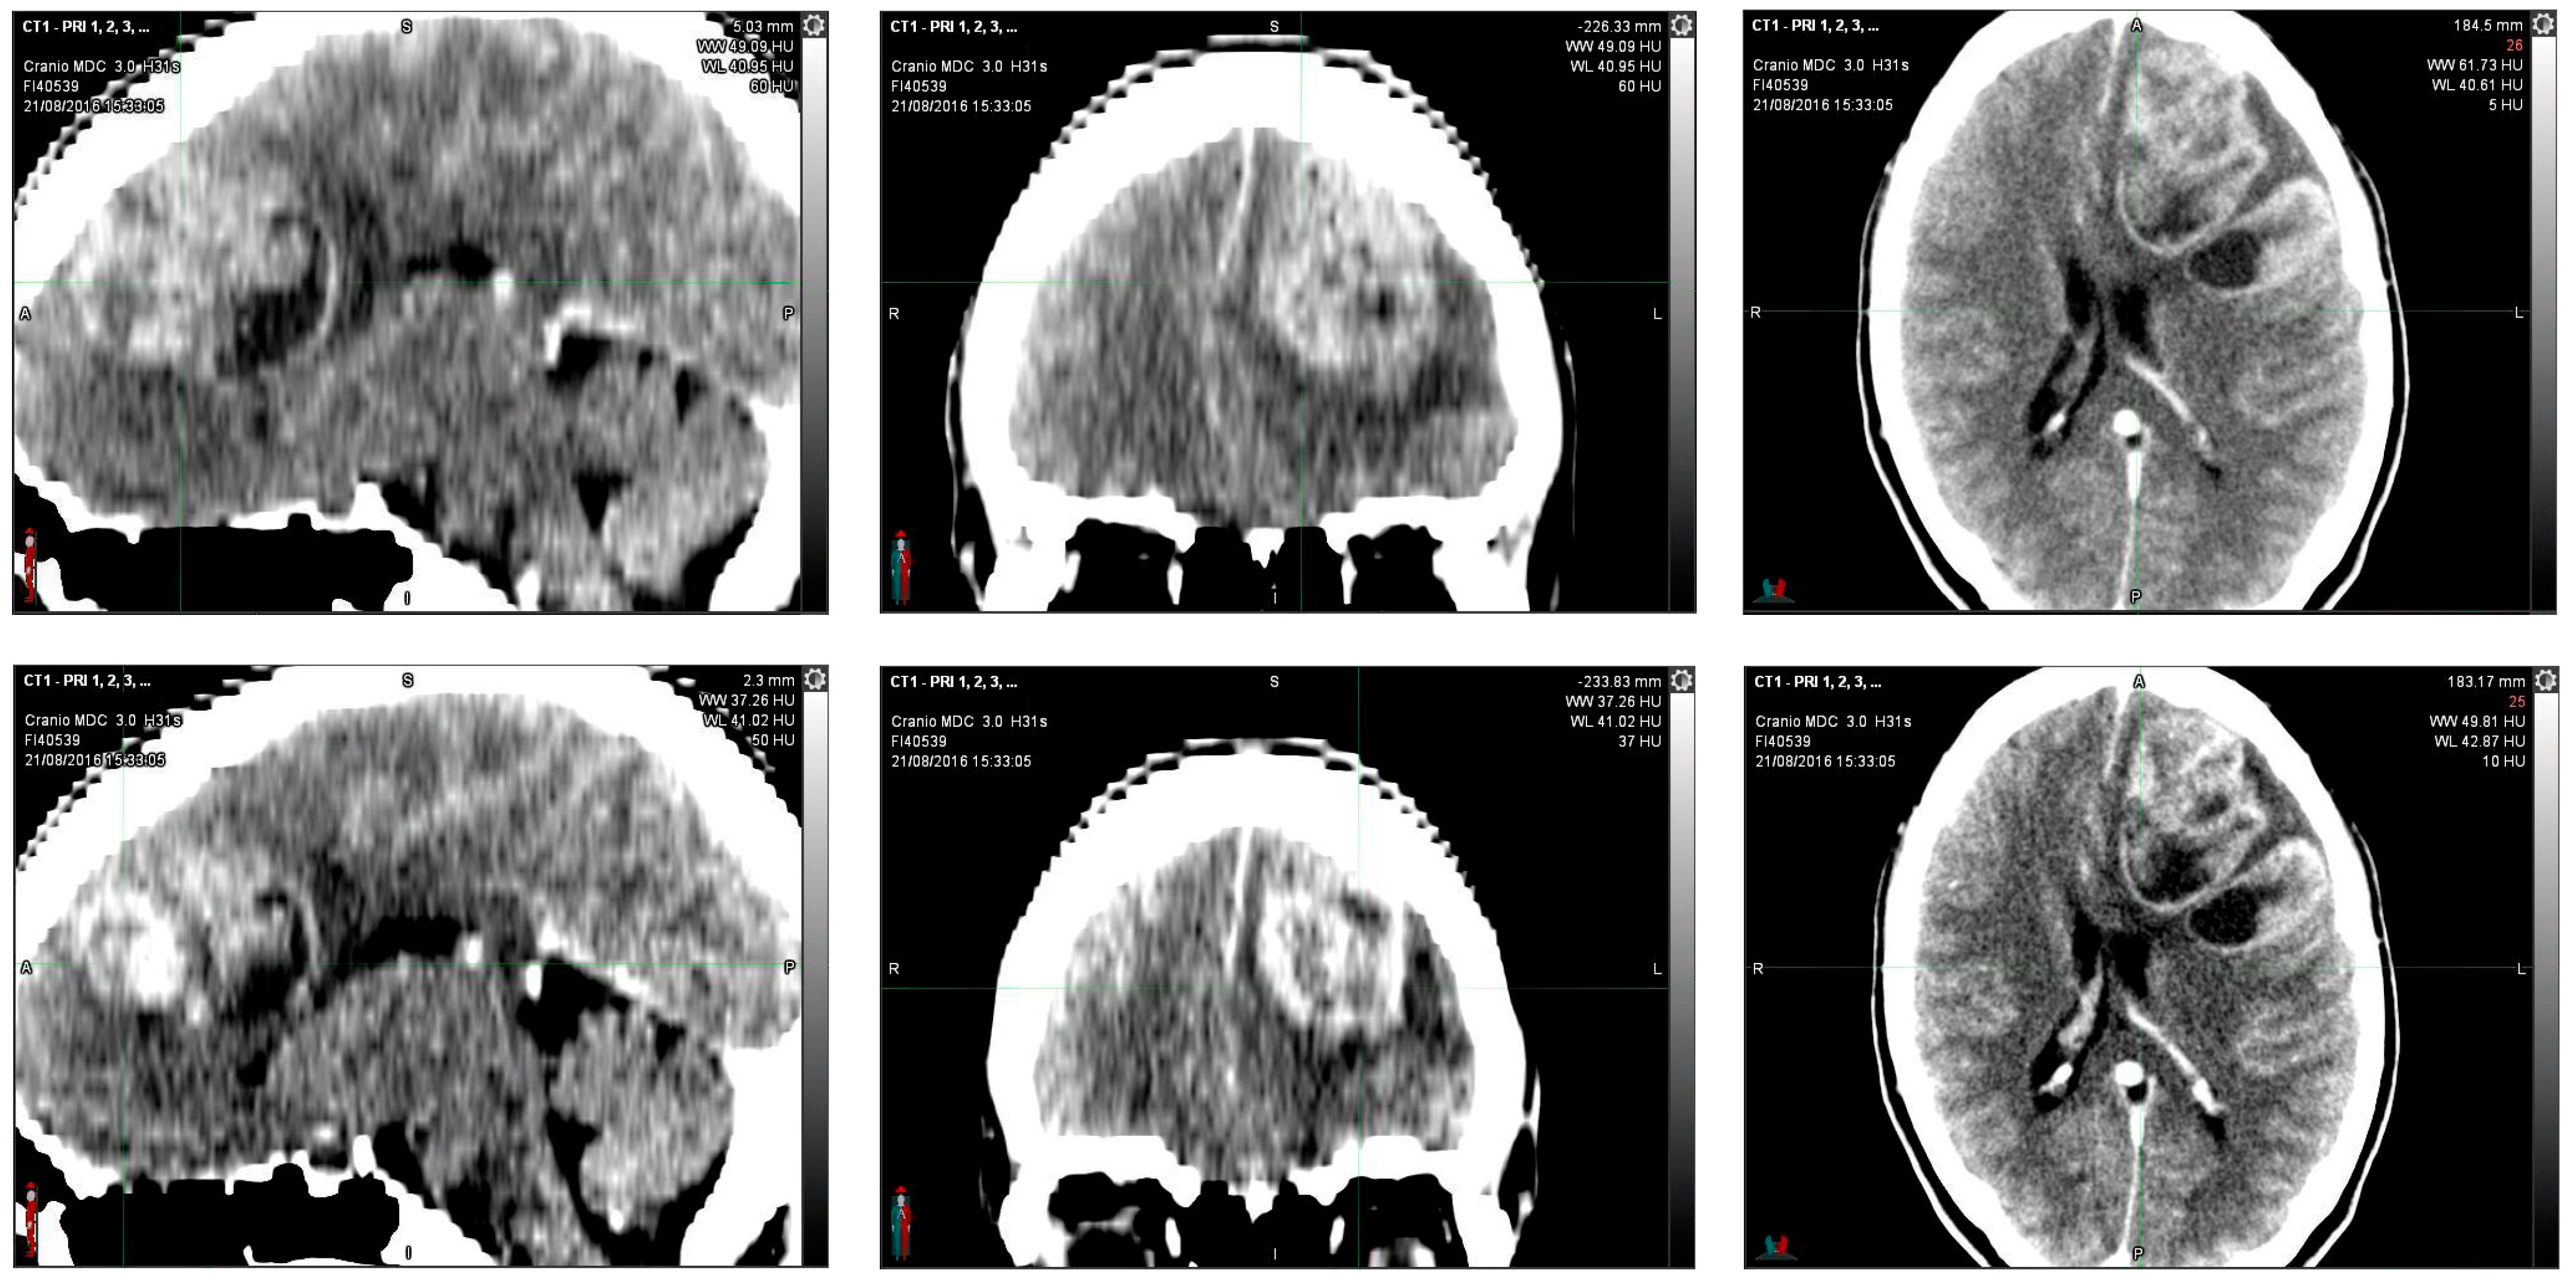

In August 2016, in the emergency department, a 36-year-old woman, after 15 days of headache and unresponsiveness to non-steroidal anti-inflammatory drugs (NSAID), underwent a computed tomography scan (CT scan). The CT scan of the brain, performed with contrast medium, showed, in the left fronto-parietal area, two voluminous formations and inhomogeneous contiguous focalities of 52 × 41 mm and 40 × 20 mm, respectively, characterized by irregular peripheral impregnation and contextual necrotic–colliquative areas, with surrounding perilesional digitiform hypodensity, compression of the lateral ventricle, and contralateral shift of the midline structures (1 cm) (Figure 1).

Figure 1.

Computerized tomography (CT) scan with contrast medium performed at initial diagnosis (21 August 2016) showed, in the left fronto-parietal area, two voluminous formations and inhomogeneous contiguous focalities of 52 × 41 mm and 40 × 20 mm, respectively, characterized by irregular peripheral impregnation and contextual necrotic-colliquative areas, with surrounding perilesional digitiform hypodensity, compression of the lateral ventricle, and contralateral shift of the midline structures (1 cm).